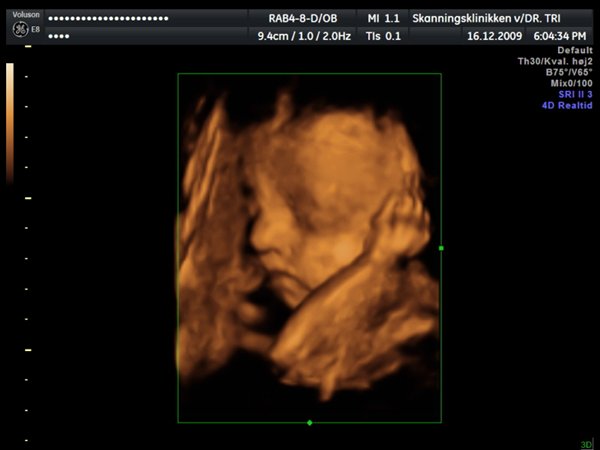

Ja, så var vi til 3D scanning med Ida igår. Og hvad kan jeg sige andet end hun er en meget træt pige

Jeg tror vi talte hun gabte mellem 10 og 11 gange under hele scanningen. Derudover havde hun meget travl med at gemme sig bag sine hænder som hun hele tiden åbnede og lukkede så det så ud som om hun vinkede

Billederne blev ikke så gode som jeg havde håbet, for lige som sin bror ligger hun meget tæt på moderkagen og med navlestregnen forand hovedet. Men de er ok, vi kan da se at hun ser sund og rask ud og at hun trives derinde.

Vedhæftede fotos (klik for at se i fuld størrelse)